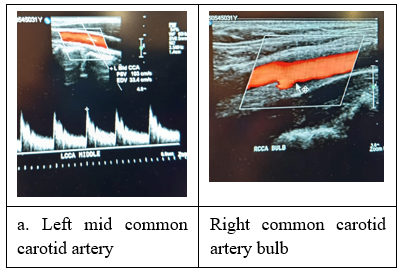

However, following this adventure, the patient suffered another episode of transient visual loss, this time of longer duration and more severe than before, lasting over 30 seconds and exhibiting a greater disability. The patient made a spontaneous recovery and consulted another ophthalmologist, who made the diagnosis of amaurosis fugax and suggested the additional investigation of ultrasonography of the carotid arteries. This was duly carried out without significant findings of wall-thickening, mural thrombi, atherosclerotic ulceration or aneurysmal dilatation. (Figure 2) Repeat of the MRI stroke package (Figure 3) and echocardiogram showed no change from the findings two years ago. Our consensus now is to go one step further and do a trans-esophageal echocardiogram (TEE) with air microbubbles as contrast. This was carried out under general anaesthesia the next day, with the finding of a patent foramen ovale which was successfully closed with a percutaneous transcatheter-deployed occluding device. (Figure 5)

Figure 4: Ultrasonographic study of carotid arterial system showing no significant disease